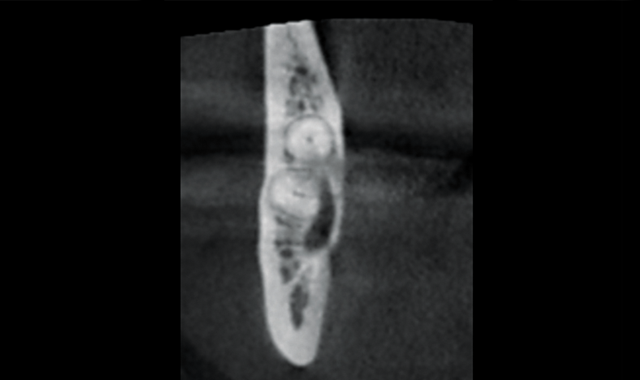

Coronal view showing proximity of nerve and coronal portion of tooth

Coronal view showing extent of lesion and proximity of nerve and apical portion of root

Through the use of 3D imaging, the patient had a much better understanding of the complexity of the issue. The coronal view of the #32 tooth shows the involvement of the lesion and the distance from the nerve to the coronal portion of the tooth. The improved distal slice shows the extremely close proximity (of lesion) to the mandibular nerve and the apical portion of the root.